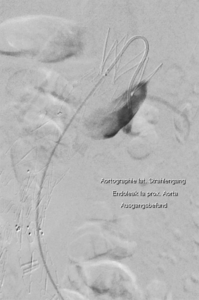

Behandlung des undichten Stentes in der Hauptschlagader:

Nach der Versorgung einer Erweiterung der Hauptschlagader des Bauches kann es zu Undichtheiten des Stentes oder zu einem Zufluss aus kleinen Arterien kommen, die zu einer gefährlichen Zunahme der Erweiterung führen können. Für die Behandlung stehen uns alle Behandlungsmethoden zum Verschließen zur Verfügung.